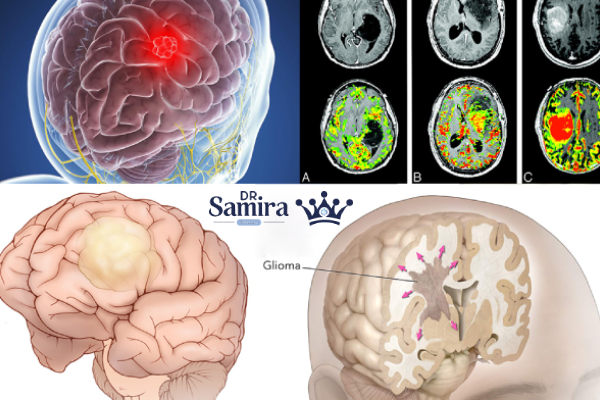

بیشتر بدانید: آستروسیتوم گرید ۴

بیشتر بدانید: تومور آناپلاستیک مغز چیست؟